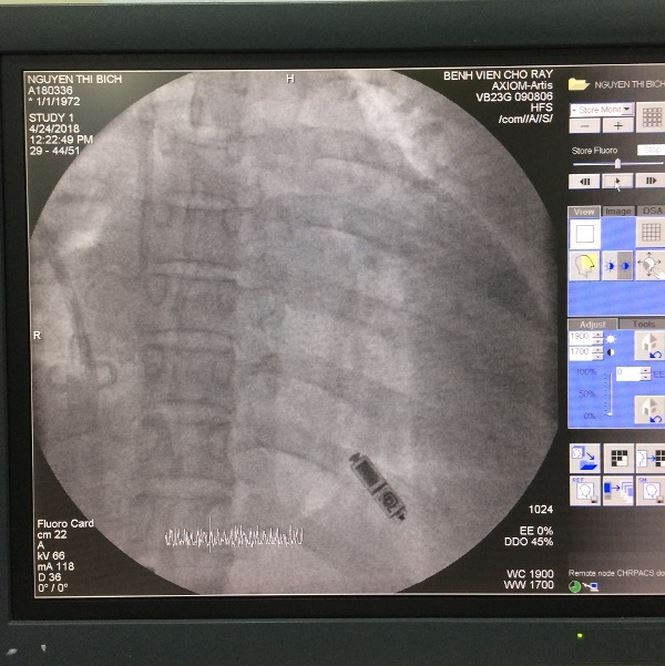

Máy tạo nhịp tim không dây MICRA |

Quá trình cấy máy MICRA |

Đây là loại máy có kích thước rất nhỏ nằm toàn bộ trong buồng thất phải của BN, được đưa vào trong buồng thất phải bằng ống thông từ tĩnh mạch đùi. Máy có dạng hình trụ tròn, tổng trọng lượng của máy là 1gam. Máy cho phép tạo nhịp tim cho người bệnh trong thời gian từ 8-10 năm.

Máy mới được cục quản lý dược phẩm thực phẩm Hoa Kỳ (FDA) cấp duyệt năm 2017. Đây hứa hẹn sẽ là một biện pháp điều trị rối loạn nhịp tim chậm tiên tiến cho những trường hợp không thể tiếp cận tim thông qua tĩnh mạch chủ trên và đồng thời mang lại tính thẩm mỹ cao vì không để lại sẹo vết mổ. Tuy nhiên chi phí máy khá cao lên đến 390 triệu đồng. Do BN có hoàn cảnh khó khăn nên các bác sĩ của BV đã vận động nguồn kinh phí từ các nhà hảo tâm để hỗ trợ.